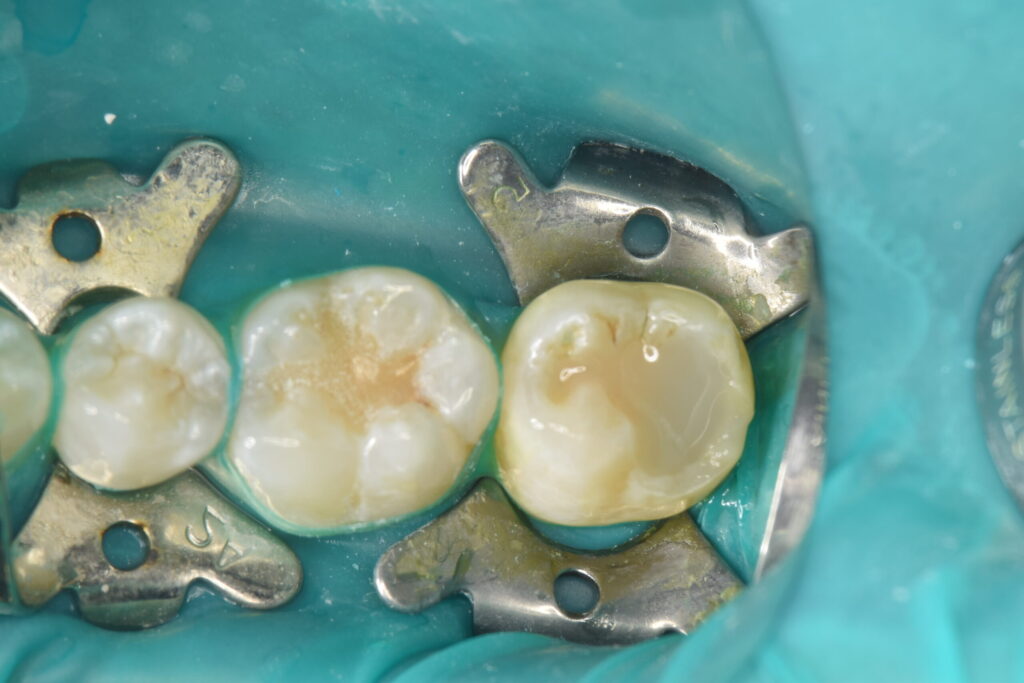

虫歯除去が終わったので、消毒を行いMTAセメントを貼付していきます。

プラスチック(レジン)での仮蓋の状態です。

1ヶ月経過をみて問題がないようでしたらオーバーレイでのセラミック治療に移行していきます。